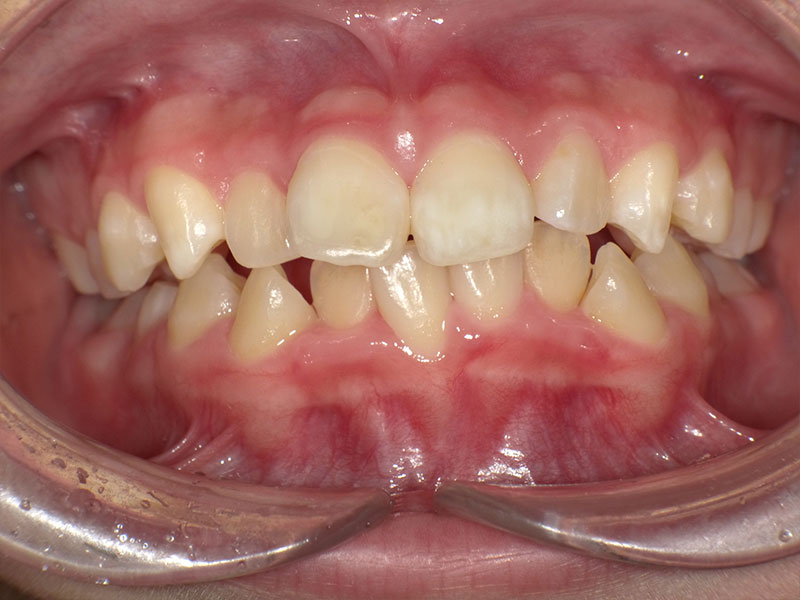

小児矯正

治療前

Before

治療後

After

年齢 10

性別 男児

主訴 下あごが出ている